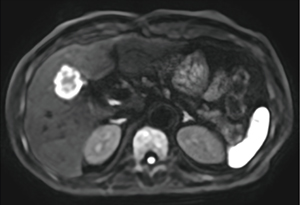

前田医師は、Vantage Centurianで撮像した転移性肝腫瘍の症例(図1)について、「臨床稼働後、最初期に撮像した画像でしたが、DWIで腫瘍が高信号に描出されるだけでなく、腫瘍中心部と辺縁部の信号のコントラストが鮮明に描出されており、Vantage Centurianの分解能の高さを実感しました」と述べる。また、膵臓の膵管内乳頭粘液性腫瘍(IPMN)の症例(図2)でも、PIQEを使用することで分解能が向上し従来画像よりも解像度が向上している。前田医師は、「PIQEの再構成画像では膵囊胞性病変の内部構造が非常にクリアになり、隔壁や充実成分のより詳細な評価が可能になるため、悪性度の評価が容易になります」と評価する。中村准教授はPIQEについて、「Vantage Centurianでは、基本画質の向上とPIQEによる再構成で、コントラストと分解能を両立した画像が得られています。画像の解像度が向上することで、病変の存在や悪性度などを悩まずに確信を持って読影することができます。不明瞭な画像では、ほかのシーケンスやモダリティの画像を確認することになるので、読影時間の短縮にもつながります」と述べる。

図1 転移性肝腫瘍(呼吸同期併用DWI)